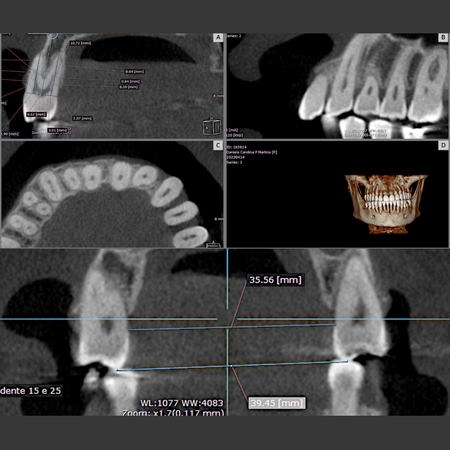

Objetivo: Avaliar as alterações, por meio de Tomografia Computadorizada de Feixe Cônico (TCFC), no osso alveolar vestibular e palatino de pré-molares superiores em indivíduos adultos jovens que foram submetidos à expansão dentoalveolar com alinhadores Invisalign ® e compará-las nos diferentes tipos faciais. Método: Quarenta e cinco pacientes (32 mulheres e 13 homens, média de 34,2 anos) realizaram expansão ortodôntica com alinhadores dentários. TCFCs foram realizadas antes (T0)...

Objective: This study aimed to evaluate changes, using Cone-Beam Computed Tomography (CBCT), in the buccal and palatal alveolar bone of maxillary premolars in young adult individuals who underwent dentoalveolar expansion with Invisalign® aligners, and to compare these changes across different facial types. Methods: Forty-five patients (32 women and 13 men; mean age: 34.2 years) underwent orthodontic expansion with clear aligners. CBCT scans were obtained before (T0) and after expansion of...